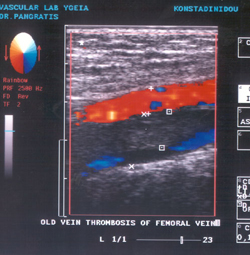

ΧΡΟΝΙΑ

ΘΡΟΜΒΩΣΗ

Με την πάροδο του χρόνου ο θρόμβος γίνεται σκληρότερος και οργανώνεται, πορεία

που συμβαδίζει με τα υπερηχογραφικά χαρακτηριστικά, αφού ο πρόσφατος θρόμβος

είναι σπογγώδης και ευμετάβλητος και καθώς παρέρχεται ο χρόνος, εξωτερική ελαφρά

ή μέτρια πίεση της φλέβας δεν συμπιέζει το θρόμβο. Σε παλαιούς θρόμβους, τα

τοιχώματα της φλέβας δεν εφάπτονται, ακόμη και εάν εφαρμοσθεί πίεση που προκαλεί

απόφραξη παρακείμενης αρτηρίας. Ένα άλλο χαρακτηριστικό επίσης είναι η αυξημένη

ηχογένεια του παλαιού θρόμβου, έτσι ώστε "όσο παλαιότερος ο θρόμβος είναι,

τόσο μεγαλύτερη ηχογένεια έχει", ενώ με την πάροδο αρκετού χρονικού διαστήματος,

ο θρόμβος έχει τέτοια υπερηχογραφική εμφάνιση, ώστε είναι δύσκολο να εξακριβωθεί

και να διευκρινισθεί από τους γύρω ιστούς. Δεν είναι σπάνιο γεγονός εξετασθείς

ασθενής με θρόμβωση προ πολλών ετών και να μην παρατηρείται φλεβικό στέλεχος

στην αναμενόμενη θέση παρά την αρτηρία. Επίσης, δεν αποφράσσουν τη φλέβα όλοι

οι παλαιοί θρόμβοι, αλλά απλώς προσκολλώνται στο τοίχωμα (επανασηρραγγοίηση).

Σε κάθε περίπτωση υπάρχει ανώμαλος υπολειμματικός θρόμβος, που θυμίζει αρτηριακή

αθηρωματική πλάκα κατά μήκος μίας ή και των δύο επιφανειών.

Σε πολλές περιπτώσεις χρόνιας θρόμβωσης παρατηρείται κάτι σαν ουρά θρόμβου,

αλλά στην περίπτωση αυτή, δεν είναι κινητή. Τέλος, ένα άλλο εύρημα χρόνιας θρόμβωσης

είναι η ανάπτυξη παράπλευρης κυκλοφορίας και είναι δυνατόν να αναπτυχθεί λίγες

ημέρες μετά το σχηματισμό του θρόμβου (επίφλεβον).